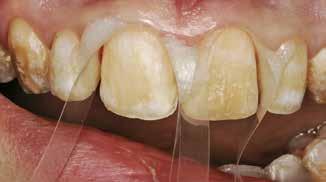

Okklusalt billede af A) over- og B) underkæbe

2. Klinisk ses tydelig slitage ind i dentinen på samtlige tænder fra 6’er til 6’er i begge kæber.

Fig. 2. Clinically, extensive wear into the dentin of all teeth in both jaws is observed.